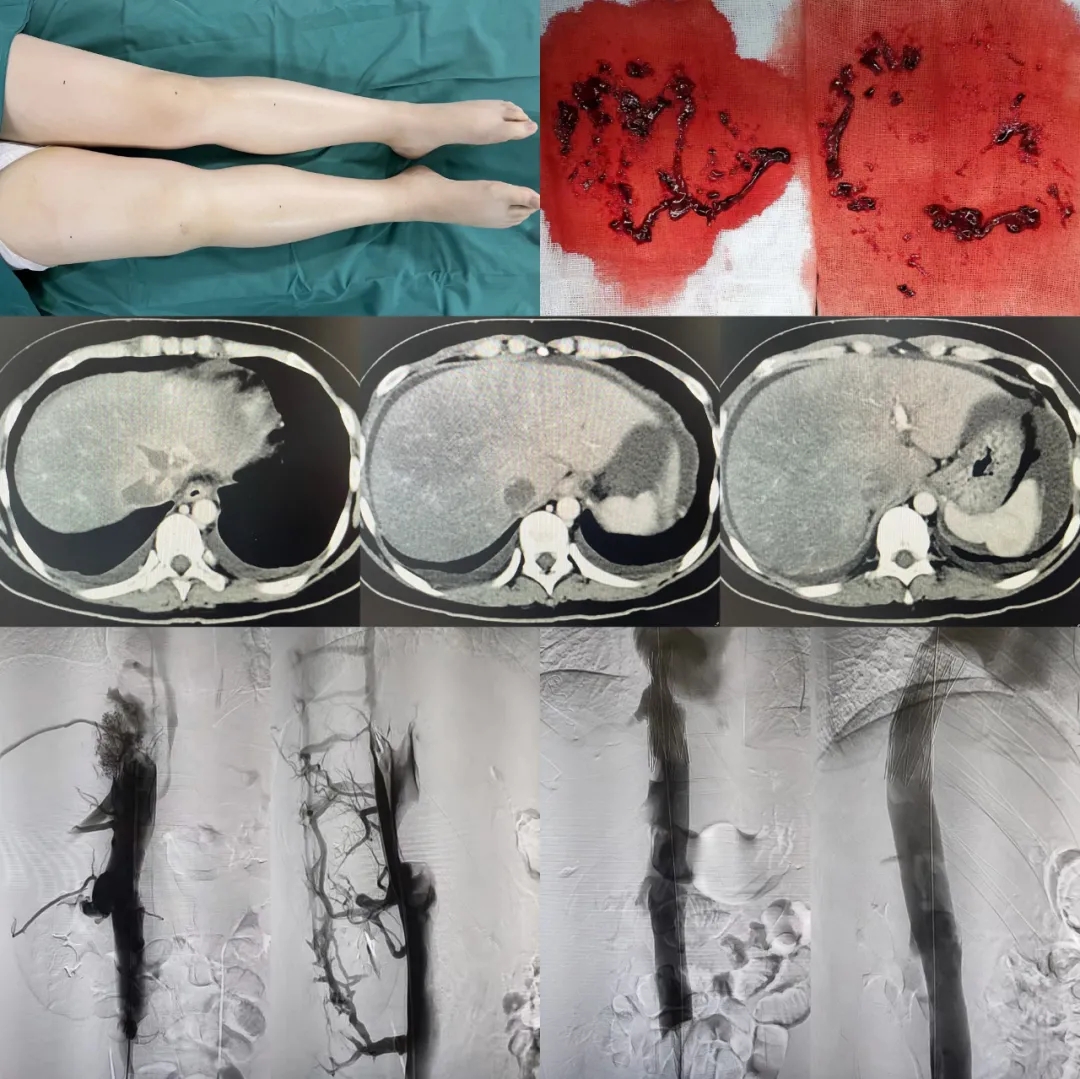

24歲患者突發(fā)少見(jiàn)病,輾轉(zhuǎn)多地病因難尋,終于在西安國(guó)際醫(yī)學(xué)中心醫(yī)院確診,5月4日,消化病醫(yī)院韓國(guó)宏院長(zhǎng)率領(lǐng)團(tuán)隊(duì)為小李進(jìn)行介入手術(shù)。目前,小李正在恢復(fù)過(guò)程中。

5月4日,在韓國(guó)宏院長(zhǎng)的帶領(lǐng)下,消化介入科醫(yī)、技、護(hù)團(tuán)隊(duì)急診行下腔靜脈的開(kāi)通治療,術(shù)中抽出了大量的血栓組織,并對(duì)近心端的血栓部位進(jìn)行了開(kāi)通治療,術(shù)后小李的惡心、嘔吐癥狀有所減輕。5月5日,韓國(guó)宏院長(zhǎng)率領(lǐng)團(tuán)隊(duì)再次為小李進(jìn)行下腔靜脈支架植入術(shù),術(shù)中造影可以看到血流終于通暢的回流到了心臟。術(shù)后小李的癥狀明顯緩解,下肢的水腫也逐漸的減輕。目前已經(jīng)恢復(fù)進(jìn)食和活動(dòng)。